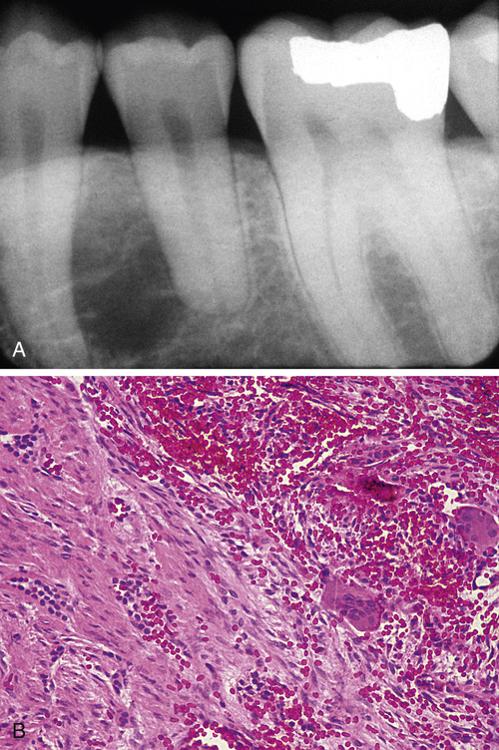

High-power view of a dentigerous cyst from a 53-year-old man. The lining demonstrates full-thickness epithelial dysplasia.

odontogenic carcinoma

A dentigerous cyst from a 53-year-old man showing islands of invasive epithelial cells in the cyst wall.